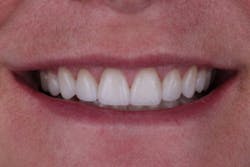

In this situation, we were able to achieve all of our functional and esthetics goals, which resulted in a happy patient (figures 22 and 23). The soft-tissue architecture was revised. The incisal edge positions and proportions were corrected. The shade, as well as the micro- and macro-esthetics, was improved. The exposed dentin and pulps of teeth Nos. 7–10 were covered and protected. Most importantly, we fulfilled the 5 requirements of occlusal stability for long-term functional success (figures 24 and 25).